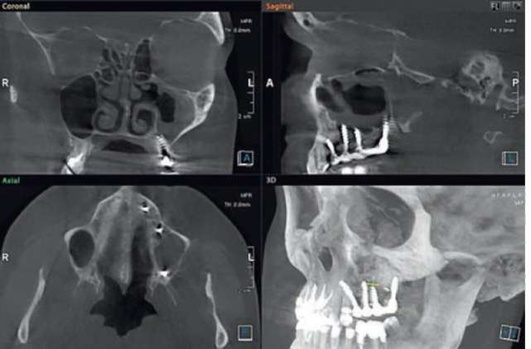

Адекватное хирургическое вмешательство и послеоперационное лечение способствуют выздоровлению. В некоторых случаях возможно самопроизвольное закрытие перфорации. Врачебная ошибка при обнаружении перфорации во время удаления зуба или вовремя нераспознанная перфорация могут привести к развитию острого перфоративного синусита. Пациенты нередко обращаются спустя несколько дней после удаления зуба с жалобами на выделения из лунки, попадание жидкости из полости рта в нос и воздуха из полости носа в рот. У львиной доли пациентов с перфорацией верхнечелюстной пазухи на основании КЛКТ были зарегистрированы деструктивные процессы в области нижней стенки ВС. Важным диагностическим этапом является проведение радиологического исследования, но вместе с тем следует указать, что проведение панорамной радиографии челюстей, черепа в аксиальной и других проекциях, зонограмм и радиологических исследований с применением контрастирующих средств на современном этапе не обоснованно в связи с низкой информативностью данных исследований. Эффекты суммации, нередко низкое качество получаемого изображения, плоскостные искажения не позволяют врачу проводить диагностику прецизионно, а учитывая уровень лучевой нагрузки, получаемый пациентом на рентгенологических аппаратах старых образцов, становится очевидно, что КЛКТ можно назвать «золотым стандартом» обследования пациентов с патологиями придаточных пазух носа (рис. 5.84, 5.85).

image

Рис. 5.84. Компьютерная томограмма до начала терапии острого одонтогенного верхнечелюстного синусита

Рис. 5.85. Компьютерная томограмма после окончания консервативной терапии

На компьютерных томограммах диагноз «острый ВС» может выглядеть очень разнообразно, но вместе с этим всегда имеются четкие диагностические критерии - наличие одонтогенной причины (инородное тело, перфорация, признаки эндоантрального синдрома), «наличие пузырьков воздуха» и признаки обструкции естественного соустья ВС.